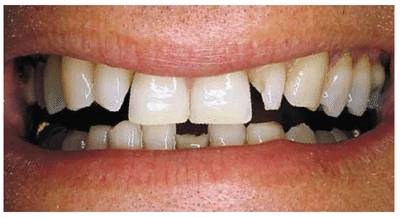

PROBLEM: This 39-year-old individual presented with diastemas between

had a marked overbite and fracture of a mandibular central incisor (Figure 23-4A

Figure 23-4A: This 39-year-old man was unhappy with his diastema, deformed laterals, and mandibular fractured incisor.

TREATMENT: A removable maxillary appliance with finger springs was

constructed to orthodontically reposition the central incisors together (Figure 23-4B). A mandibular lingual appliance

was also used to upright the molars to regain lost vertical dimension and

realign the crowded mandibular anterior teeth. After completion of orthodontic

treatment, the maxillary central incisors were splinted together with composite

resin to prevent future drifting and reformation of the diastema (Figures 23-4C

and D). The

adjacent maxillary lateral incisors were crowned to assist the stabilization of

the central incisors and restore symmetry to the maxillary arch, eliminating

their "peg-lateral" shape (Figure 23-4E). In addition, the mandibular left

central incisor was crowned. The final smile achieved improved esthetics,

health, and function (Figure 23-4F

Figure 23-4B: A removable maxillary appliance with finger springs was used to bring the central incisors together.

Figure 23-4C and D: The maxillary central incisors were bonded together with composite resin to help retain them in their new position.

Figure 23-4E and F: The adjacent maxillary lateral incisors were crowned to help hold the central incisors in place and restore symmetry to the maxillary arch. The mandibular left central incisor also was crowned to complete the esthetic result.

RESULT: The success of this case is based

on a close working relationship with the orthodontist to accomplish necessary

repositioning before restorative procedures are begun. The final esthetic

result could not have been achieved by crowning the four incisors alone. If

orthodontics had not been employed, either the central or lateral incisors

would have necessarily been overcontoured; in addition, the overbite would not

have been corrected to any appreciable extent.